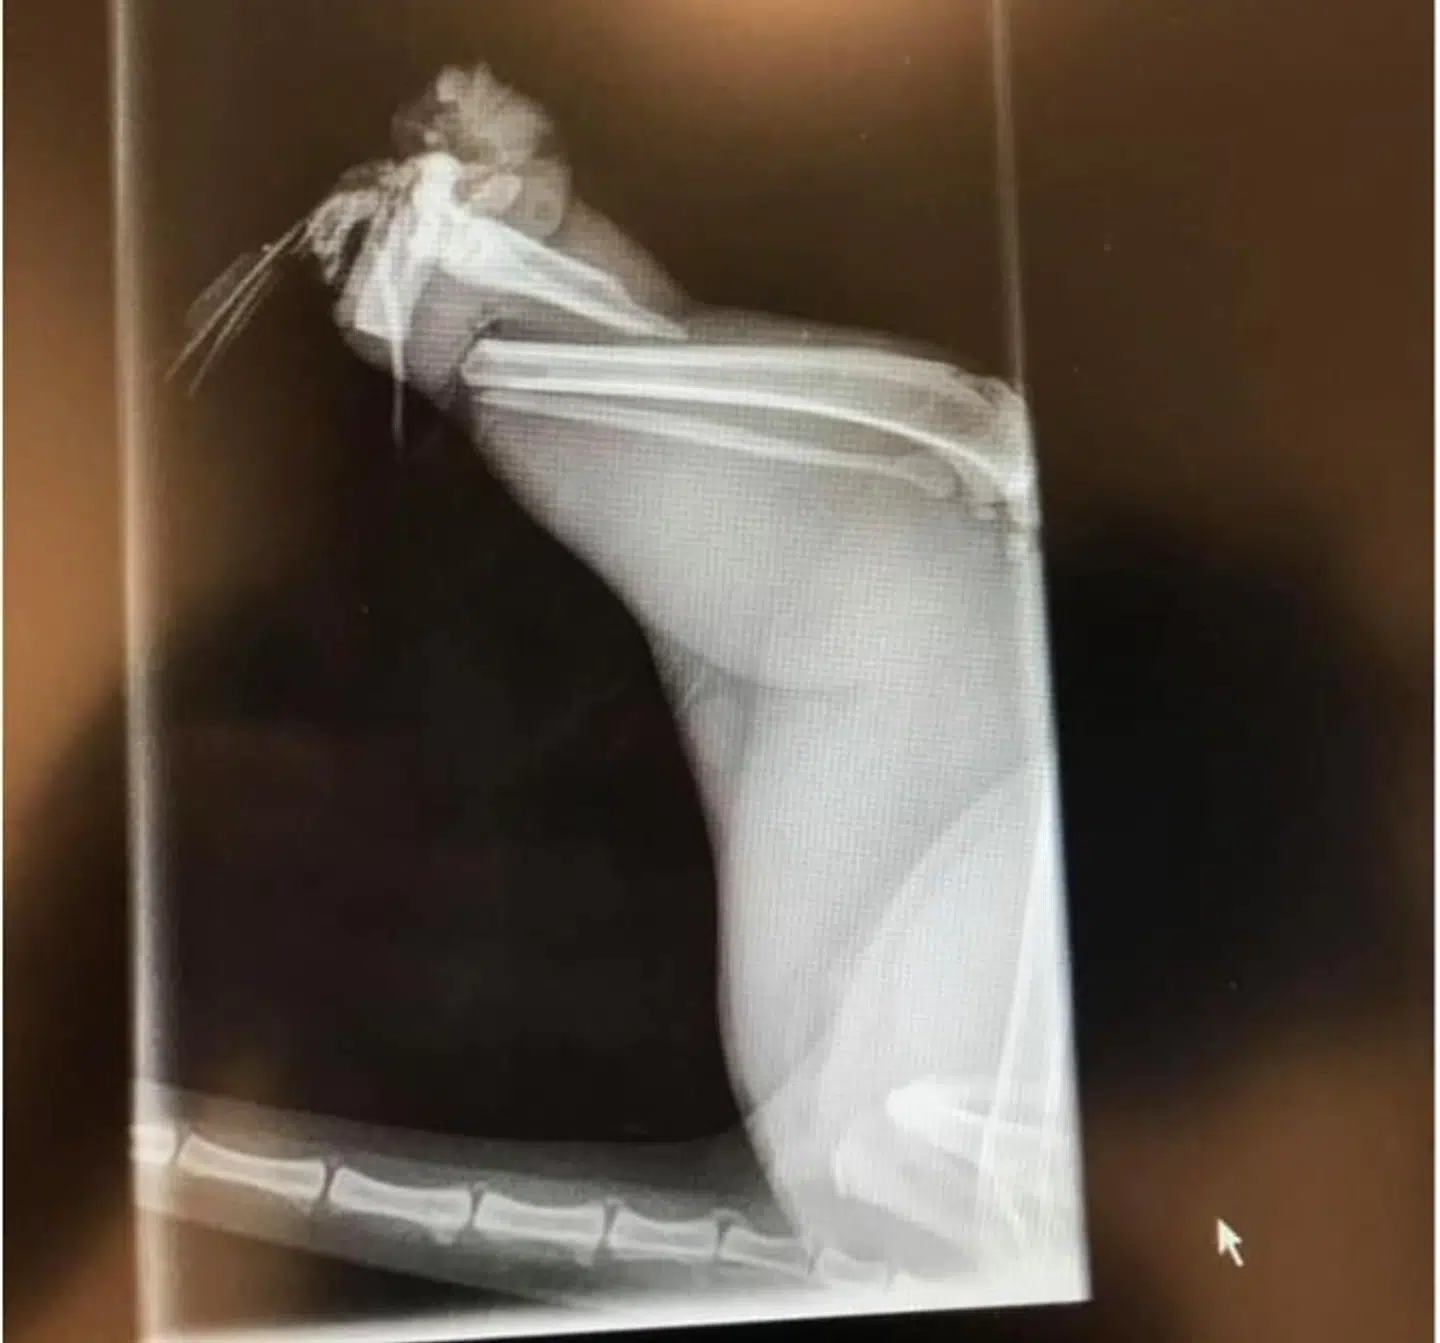

De har alle mistet det ene eller begge bagben.

Ligesom de andre fire katte manglende hun også bagben.

Begge bud er dog ret tvivlsomme, da kattene ikke har brækket deres ben. Nej, de er simpelthen kappet af.